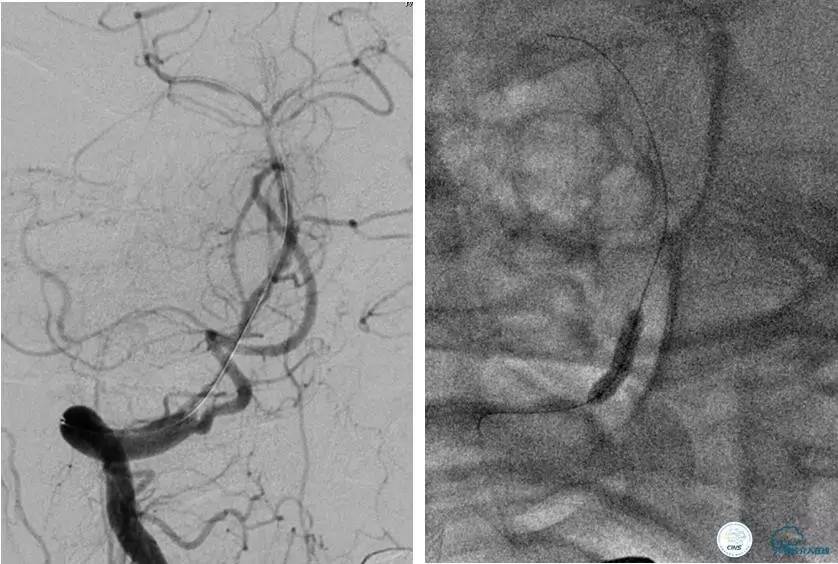

患者:53岁男性,反复脑梗死3个月。

▼给予球囊扩张成形,闭塞段较长,决定药物治疗观察,二期再给予支架治疗。

▼药物治疗1个月,再次发作。再次来我院支架治疗。

▼支架术后,效果好。

因此,某些患者分期治疗也具有合理性。